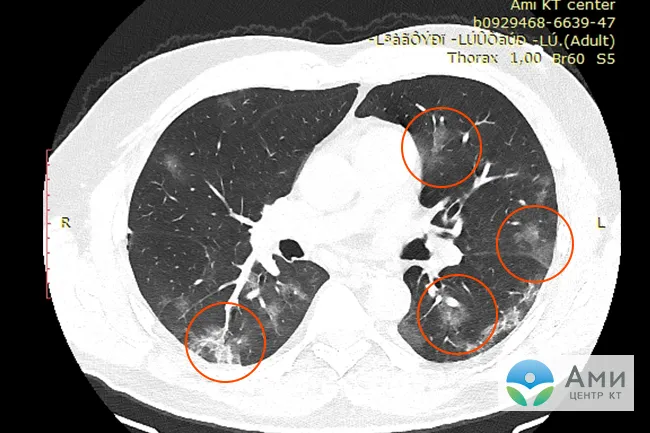

Симптом «матового стекла» (инфильтраты) при вирусной пневмонии на посрезовых КТ-сканах